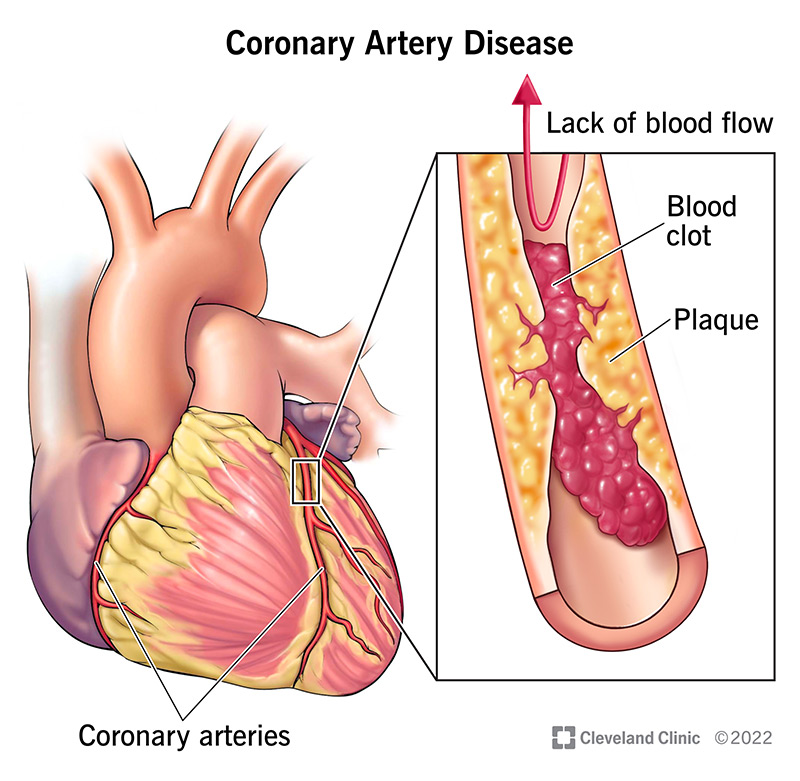

Coronary Artery Disease: Symptoms, Causes & Treatment

Heart Attack